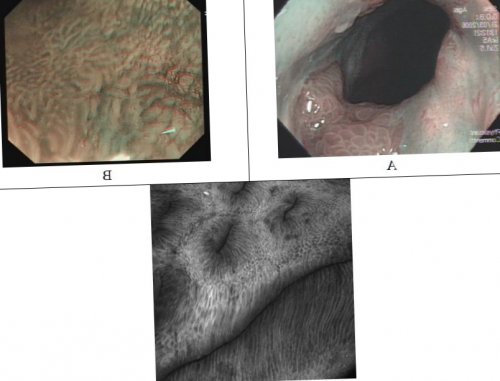

Для оценки циркулярного (С) поражения и максимальной протяженности (М) по складкам ПБ применяются Пражские критерии (The Prague C&M Criteria) (рис.2). Данная система оценки степени распространенности КМ имеет высокий коэффициент надежности в случае сегмента метаплазии, длиной более 1 см. При ультракоротком сегменте метаплазированного эпителия коэффициент надежности резко снижается до 0,22.Рис.1 Эндоскопическая диагностика ПБ. А. Эндоскопическое исследование в режиме NBI – виллезная архитектоника ямок слизистой оболочки в пределах сегмента метаплазированного эпителия – признак КМ. B. Эндоскопическое исследование в режиме NBI с увеличением в 150 раз– нерегулярная архитектоника ямок и деформация внутрисосочковых капиллярных петель – признак дисплазии эпителия высокой степени в пределах сегмента ПБ C. Эндомикроскопия (увеличение х1000) – темные бокаловидные клетки и удлиненные ядра эпителиоцитов кишечного типа – признак КМУзкоспектральная эндоскопия (NBI – Narrow Band Imaging) – эндоскопическая технология, в основе которой лежит освещение слизистой оболочки световым пучком с узким спектральным диапазоном и длиной волны 415 +/- 30 нм (исключение красной составляющей из спектра излучаемого эндоскопом света), что позволяет контрастировать капиллярный рисунок и архитектонику ямок слизистой оболочки ПБ. При использовании NBI можно выделить 5 типов архитектоники ямок метаплазированного железистого эпителия в пищеводе: виллезный (в виде «черепичек»), гребенчатый (удлиненные гребни) церебральный («мозговидный»), овальный (округлый) и нерегулярный (стертый) (Рис. 1А) При этом, виллезная архитектоника ямок слизистой оболочки пищевода может соответствовать кишечной метаплазии плоского эпителия, церебральная – кардиальному желудочному эпителию, овальная – фундальному желудочному эпителию и нерегулярная или отсуствующая – тяжелой дисплазии эпителия ПБ и ранней аденокарциноме на его фоне (104, 105). Наилучшие результаты получаются при сочетании узкоспектральной эндоскопии (NBI) с инстилляцией 1,5% раствора уксусной кислоты. При таком методе исследования достигается высокая точность дифференциальной диагностики различных типов метаплазированного эпителия в пищеводе, включая участки эпителия с неопластической прогрессией .Эндоскопическое исследованиеКлинические симптомы у больных с ПБ не отличаются от таковых при других формах ГЭРБ. Характерные клинические признаки, указывающие на развитие ПБ у больных ГЭРБ, отсутствуют.При наличии дисплазии эпителия ПБ риск малигнизации варьирует в зависимости от степени дисплазии и ее распространенности (количества ее очагов) [2,16,17,19]Значительное влияние на развитие ПБ оказывает характер питания и наличие метаболического синдрома: употребление жира с пищей способствует развитию ГЭРБ, ПБ и АКП, наличие метаболического синдрома повышает риск развития ПБ в 2 раза.Причины и факторы, запускающие развитие метаплазии и дисплазии в эпителии слизистой оболочки пищевода до сих пор в достаточной мере не изучены. Считается, что основным фактором, определяющим развитие ПБ является многолетний анамнез ГЭРБ: при длительном воздействии кислоты и компонентов желчи на слизистую оболочку пищевода стволовые эпителиальные клетки, расположенные по ходу базальной мембраны плоского эпителия и протоков эзофагеальных желез, могут дифференцироваться не в характерный для пищевода многослойный плоский эпителий, а в более устойчивый к воздействию кислоты и желчных кислот цилиндрический эпителий. В условиях продолжающегося повреждающего воздействия на метаплазированный эпителий кишечного типа формируется клон клеток с нарушенными механизмами апоптоза (запрограммированной клеточной гибели)– дисплазия эпителия и, впоследствии – АКП.• Длительный (> 13 лет) анамнез симптомов ГЭРБ (изжога)Факторы риска развития пищевода Баррета

Наибольшую диагностическую точность в выявлении ранних неопластических изменений слизистой оболочки ПБ представляет сочетание оптической увеличительной эндоскопии в 150 раз с технологией NBI. Подобное комплексное исследование позволяет не только визуализировать архитектонику ямок слизистой оболочки ПБ, но и оценивать структуру капиллярной сети, выявлять изменения формы, размера, упорядоченности расположения капиллярных петель. Выявление значительной гетерогенности, расширения, деформации IPCL может свидетельствовать о наличии неопластических изменений эпителия в исследуемом участке слизистой оболочки ПБ . (Рис.1B)В течение многих лет «золотым стандартом» эндоскопической диагностики ПБ являлась эзофагогастродуоденоскопия с множественной 4-х квадрантной биопсией измененной слизистой оболочки пищевода с интервалом в 2см . . Однако, в настоящее время доказано, что рутинная эзофагоскопия позволяет лишь высказать предположение о наличии ПБ, но ее диагностическая точность в выявлении именно КМ эпителия слизистой оболочки пищевода, дисплазии эпителия, равно как и ранней аденокарциномы, не превышает 60%[70, 77]. Косвенными эндоскопическими признаками диспластических изменений эпителия слизистой оболочки ПБ могут служить изменения цвета и рельефа, причем на очень ограниченных участках — диаметром 2-3 мм: очаги гиперемии с подчеркнутым сосудистым рисунком, ее очаговые утолщения или мелкие углубления, эрозированные и изъязвленные участки в пределах сегмента ПБ .ПБ на фоне эрозивно-язвенного эзофагита может сопровождаться стойкими и выраженными симптомами ГЭРБ. У части пациентов с ПБ определяются менее интенсивные симптомы (изжога, регургитация, загрудинные боли), чем при рефлюкс-эзофагите, а почти у половины (40-45%) клинические симптомы отсутствуют.• при низкой степени дисплазии – 0,8-1,9% в год;Риск злокачественной трансформации при пищеводе БарретаДополнительными, но не менее важными факторами, повышающими риск метаплазии эпителия слизистой оболочки пищевода являются курение, ожирение и генетическая предрасположенность.• Высокая секреция соляной кислоты и высокое содержание желчных кислот в рефлюктатеОсновными факторами, способствующими развитию КМ слизистой оболочки пищевода являются[1,2]: